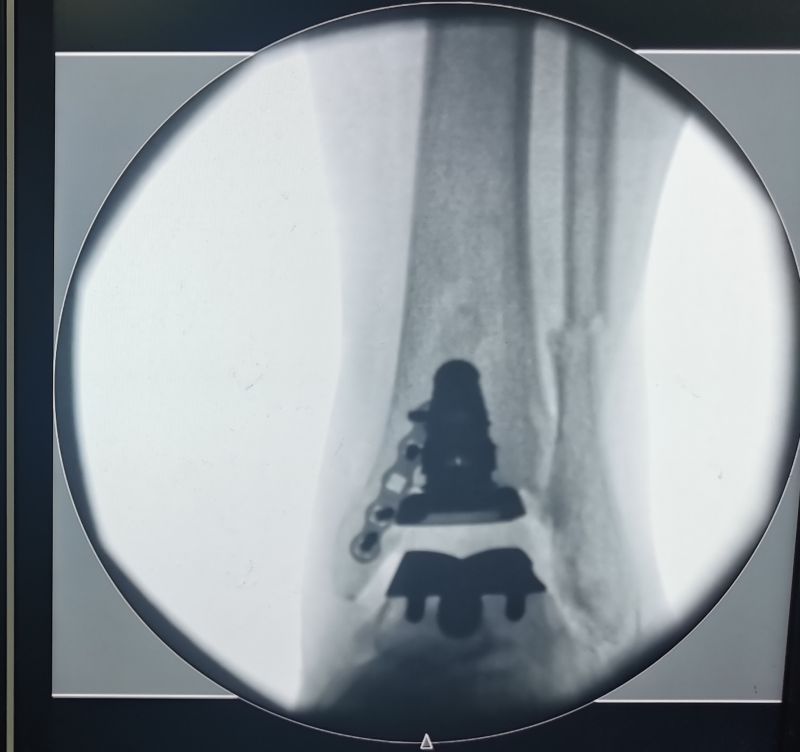

踝关节置换术中透视

经过周密的术前准备,在北京大学人民医院徐海林教授的指导下,在麻醉科的大力协助下,足踝外科团队为患者实施了全踝关节置换术。手术过程精准仔细、环环相扣,历经3小时右踝全踝关节置换术顺利完成。术后患者病情平稳,目前正处于恢复中。